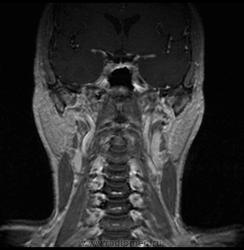

06.06.2011 МРТ - головы и шеи.

Пацентка 36 лет, с жалобами на припухлось в околоушной области справа.

В глубокой доле  правой околоушной железы  на фоне неизмененной паренхимы зона  гетерогенного по Т2, гипоинтенсивного по Т1  с единичными гиперинтенсивными включениями.При контрастировании- накопление контраста диффузное неоднородное и по периферии.Рискну предположить злокачественное образование ( аденокарцинома) с низкой степенью злокачественности( есть капсула, экспансивный рост).Сильно не расстреливайте.

Проблема в том, что перед челюстно-лицевым хирургом стоит распространенность любого объемного процесса, в данном случае все упирается в возмможную травму лицевого нерва и конечно же с дальнейшим его парезом, а ведь женщина  еще молодая. Образование имеет тонкостенную оболочку, по структуре неоднородно, с наличием кальцината, при этом МР-сигнал от окружающих анатомических структур(как костных так и мышечных) не изменен, т.е. об инфильтративном росте речи не идет, в какой то степени доброкачественное. В конкретном случае лицевой нерв с ретромандибулярной веной просто несколько оттеснен.

По гистологии аденома околоушной слюнной железы, но после удаления пока сохраняется парез лицевой мускулатуры, возможно временный.